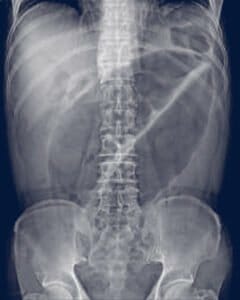

Diagnosis may be confirmed if an abdominal plain film shows the classic “coffee bean” shaped colonic dilatation in the left upper quadrant (figure 2). A barium enema may be used in cases not resolved by plain films. A birds beak may be seen. However, the use of a barium enema is to be avoided if there is a concern about a colonic perforation, or if the abdominal exam points to the need for an immediate surgical procedure.